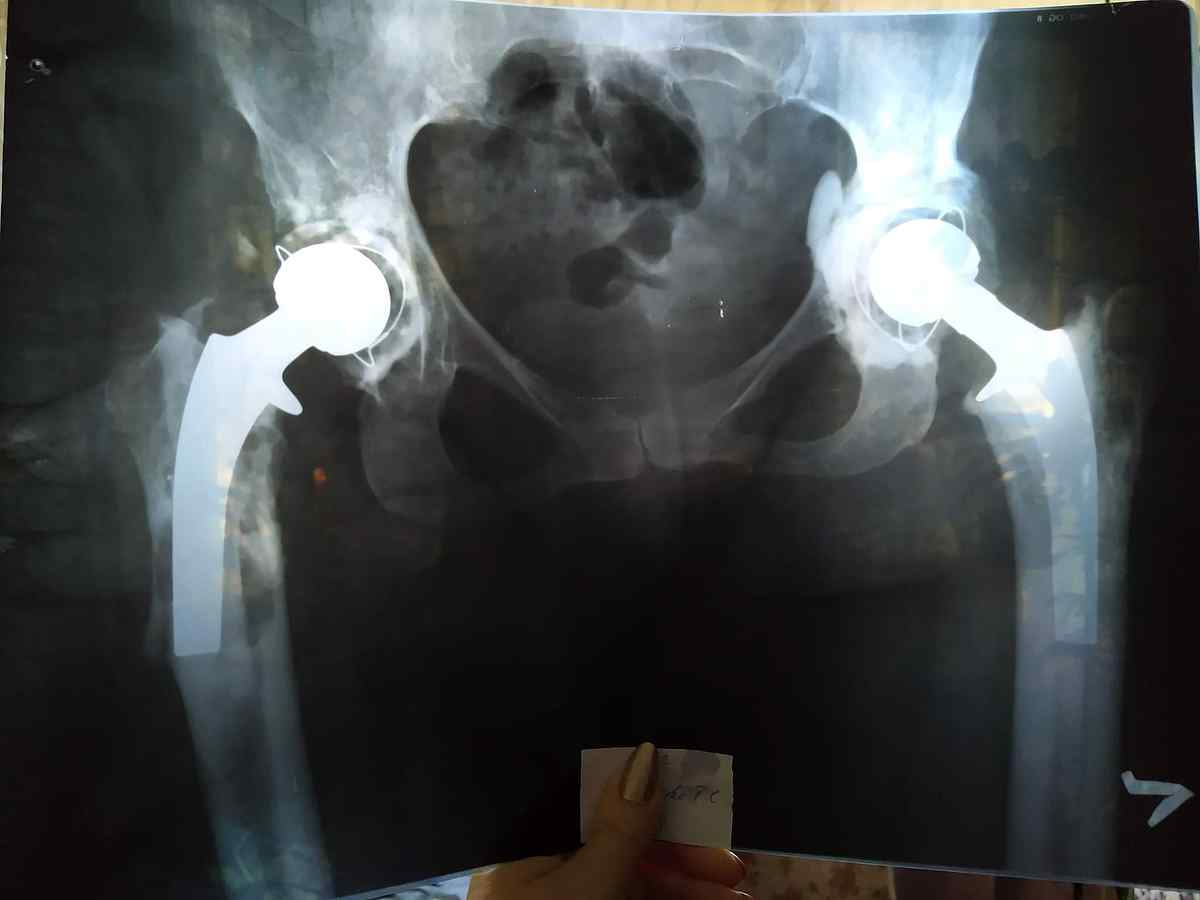

Вінничанка терміново потребує грошової допомоги на заміну ендопротеза тазостегнового суглоба. У Тетяни Ігнатьєвої закритий перелом правої стегнової кістки, нестабільність тазового ендопротезу правого кульшового суглобу. 14 років тому їй робили цю операцію, цього року потрібно знову. Сьогодні вона немає змоги її оплатити, повідомляє Vlasno.info.

17 грудня Тетяна Ігнатьєва зробила рентген. З отриманих знімків лікарі сказали, що необхідно робити терміново операцію, яка коштує від 100 тисяч гривень. Ця сума є великою для родини жінки.

– Оперувати буде професор, який проводив операцію 14 років тому. На жаль, гарантія на протез десять років, тому операцію потрібно робити через роки. Наразі бюджетних протезів на цей рік немає. Бюджет на наступний рік не складено, тому в чергу ставати немає часу, – розповідає студент ДонНУ ім. В. Стуса Олександр Ігнатьєв.